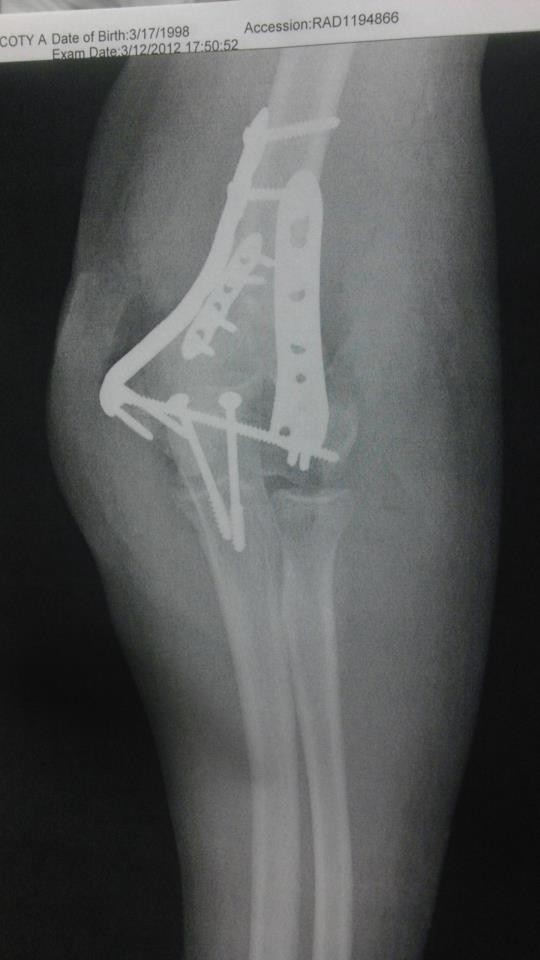

Cody Rust: View Profile